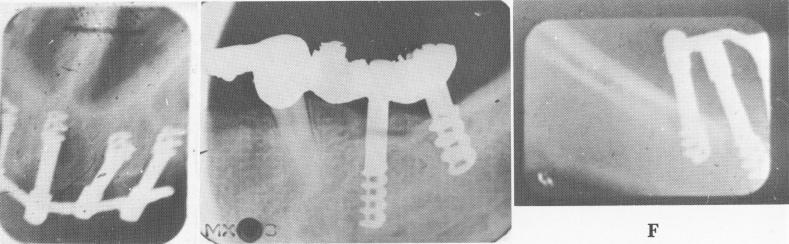

Fig. 14-16. A to C, These radiographs reveal resorption of bone directly under the superficially placed shoulders of the blade implants. D to F, Implants that are not parallel to each other and to the remaining teeth can cause difficulty in seating the bridge. Also, and even more important, is that if they are not placed vertical to the occlusal forces, bone breakdown can occur as a result of unequal destruction of the forces that are brought to bear upon them.

1 Bone resorption under superficially placed shoulders of blade implants